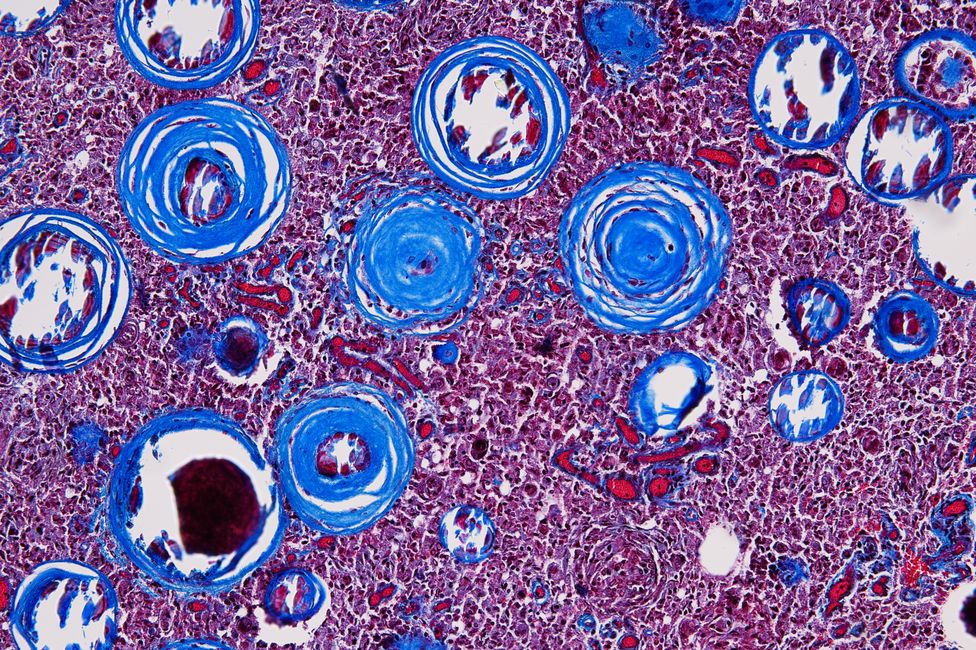

Die forensische Histologie nimmt eine wesentliche Rolle im Rahmen von gerichtlichen Leichenöffnungen ein, da mit spezifischen histochemischen und immunhistochemischen Färbemethoden Aussagen zur Todesursache, z.B. sauerstoffmangelbedingte frühe Organschädigungen, erkannt, aber auch Altersbestimmungen von Verletzungen und Vitalitätsprüfungen durchgeführt werden können.

Im Gegensatz dazu werden in der Pathologie spezielle Untersuchungsmethoden, insbesondere immunhistochemische Techniken, eingesetzt, um differenzierte Diagnosen von Erkrankungen als Grundlage für notwendige therapeutische Maßnahmen zu erstellen.